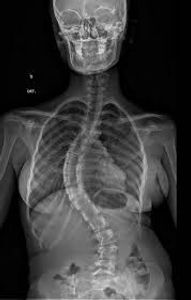

Olá, pessoal talvez vocês já saibam que estou arrecadando fundos para minha cirurgia de escoliose, está causa é muito importante para mim porque já não consigo mais viver com tantas dores e pressão no peito decorridas desse problema, isso afeta toda a minha vida pois preciso trabalhar para cuidar das despesas da casa porque minha mãe e irmã não conseguem lidar com tudo, nem temos condições para pagar uma cirugia pois é muito caro, somos uma família de três mulheres do sertão da Paraiba, mais precisamente de uma cidade do interior chamada Pombal. Estarei feliz com qualquer apoio que conseguir, preciso de ajuda para alcançar o objetivo do meu projeto de arrecadação, pois faz dois anos que espero pelo sus essa cirugia e ela ainda não saiu, eles sempre dizem que têm um fila de espera e que vai demorar um pouco, mas já não consigo lidar com isso. necesito de (50.000.00) para despesas de deslocamento (do interior para a capital), cirugia e pós - operatório. Você estaria disposto a contribuir com a minha campanha de arrecadação de fundos? Qualquer quantia que você doar fará muita diferença para mim. [Chave Pix: (83) 99692-1100 ou agência: 0001, conta: 55082633, banco:0260 ou [3588366@vakinha.com.br], Seria um prazer conversar com você sobre a minha campanha, portanto, não deixe de fazer contato. abraços, atenciosamente, Danyele.